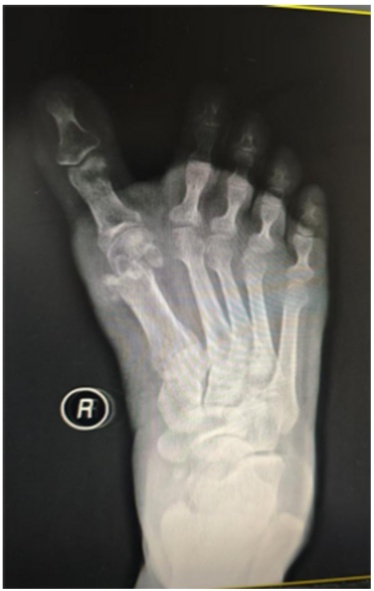

患者女,46岁。因“右足进行性行走疼痛、伴踇趾外翻畸形8月余”来我科就诊。专科检查:右侧第一跖趾关节外翻畸形(见图1(a)图1(b)),活动受限,拇囊部位压痛明显,无纵向叩击痛。第一跖趾关节松弛,活动后疼痛加重。前足功能AOFAS评分为45分,神经血管检查正常,其余肢体未见异常。既往史无特殊,检验结果未见异常。右足部X线片显示:右侧第一跖趾关节对位欠佳呈外翻改变,外翻角约33˚,第1、2跖骨间夹角约为9˚,第一近节趾骨近端可见骨质增生边尖(见图1(c))。入院诊断:右足拇外翻合并第一跖趾关节半脱位。完善相关检查后,行右足拇外翻切开截骨矫形克氏针内固定术。手术过程:麻醉生效后,患者取仰卧位,绑止血带,右下肢常规消毒铺巾,打止血带,C臂透视确认截骨位置,截骨位置靠近跖骨颈的内侧隆起处。皮肤切口:取右足背内侧第一跖趾关节处纵切口,切一长约2 cm皮肤切口。操作过程:电刀分离皮下组织至关节囊,电凝止血,切除增生关节囊,显露内侧跖趾关节,用摆据距跖骨远端2 cm处垂直于跖骨干横向截骨,将跖骨头向外侧推移,将第1根金属骨针沿远端截骨断端前内侧皮下置入并从拇趾趾甲近端内侧皮缘穿出,将布巾钳插入跖骨截骨近端髓腔,再从拇趾趾甲内侧将金属骨针置入跖骨干髓腔基底部内固定,透视确认足拇外翻畸形矫形满意,将第2根金属骨针从跖骨内侧缘距离跖骨近端截骨面1 cm处上斜形插入,从远端截骨面中点穿过,从跖骨远端外侧皮质穿出(见图1(d)图1(e)),固定截骨远端,C臂透视见拇外翻纠正,内固定位置可(见图1(g))。逐层缝合切口,以敷料固定包扎保护拇趾于中立位(见图1(f)),术后第2天复查X线(见图1(h))。术后6周来院拆除第2根金属骨针后,复查X线示恢复可(见图1(i)),术后7周来院拆除第1根金属骨针,复查X线片示恢复可(见图1(j)),术后3月我院复查足部情况(见图1(k))。

(a) (b) (c) (d)

(e) (f) (g)

(h) (i) (j) (k)

(a) (b) 术前右足外观;(c) 术前片X线片:右足中度拇外翻并第一跖趾关节半脱位;(d) 术中克氏针固定位置;(e) (f) 皮肤切口:右足背内侧第一跖趾关节处纵切口,切一长约2 cm;(g) C臂透视确认脱位复位满意,内固定位置可;(h) 术后右足正侧位x片显示:第一跖趾关节对位良好,跖骨断端对线可,轻度向内移动约1/4;(i) 术后6周患者右足部X线复查情况;(j) 术后7周右足部X线复查情况;(k) 术后3月右足部复查情况。

Figure 1. Patient’s imaging data

1. 患者影像学资料